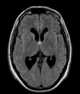

Colloid cyst of third ventricle

A colloid cyst is a non-cancerous tumor in the brain. It consists of a gelatinous material contained within a membrane of epithelial tissue. [Source: Wikipedia ]